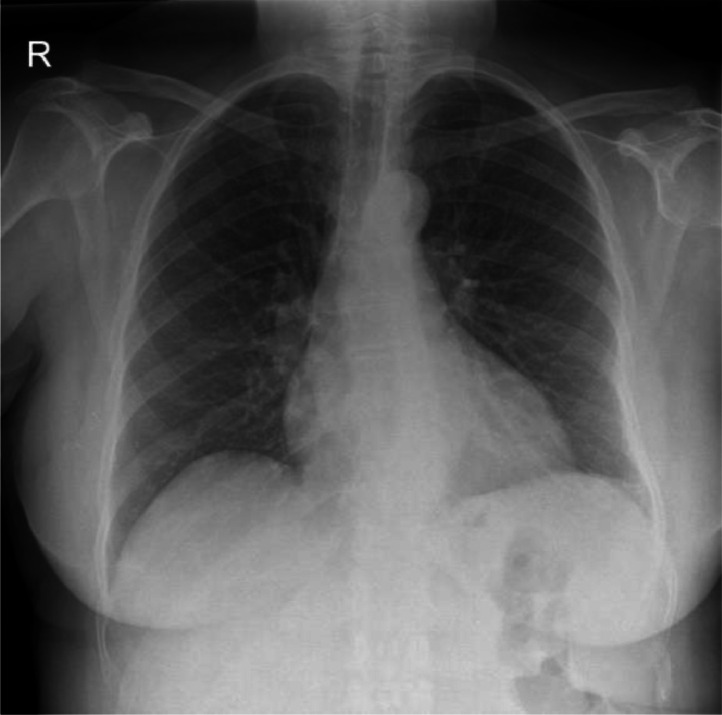

Scrub typhus, caused by Orientia tsutsugamushi, is a rickettsial infection transmitted by mite bites, often underdiagnosed in travellers from endemic regions. This case report describes a 65-year-old female with hypertension who developed severe scrub typhus after a trip to Sri Lanka. She presented with fever, myalgia, headache, fatigue and a scabbed lesion. Initial tests showed neutrophilia, lymphocytopenia and elevated liver enzymes. Malaria was ruled out, and empiric treatment with intravenous Tazocin was initiated. On day 5, she developed Clostridium difficile infection, requiring a switch to oral vancomycin. By day 5, her condition worsened with hypoxia, hypotension, oliguria and renal failure. Chest X-ray revealed bilateral infiltrates and subsequently, she was transferred to critical care. Tests showed positive IgM test for O. tsutsugamushi. Oral doxycycline was started, resulting in rapid improvement. PCR confirmed scrub typhus. This case underscores the importance of early diagnosis and treatment with doxycycline in travellers from endemic areas presenting with febrile illness.